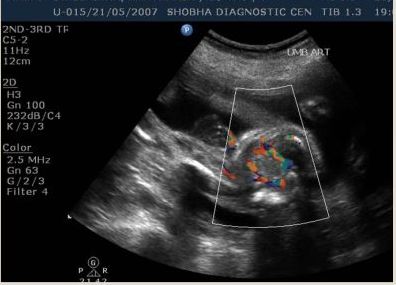

Routine Sonography

To know growth and general condition of the baby.